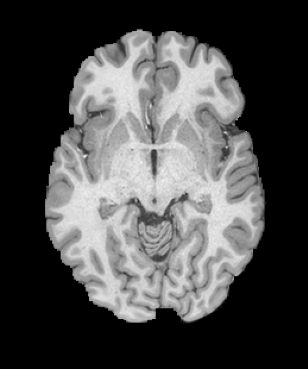

We evaluate on several datasets, where we can compare to earlier registration approaches. We use the network with inverse-consistent SVF networks backed by U-Nets and inverse-consistent affine networks backed by ConvNets222Specifically, networks.tallUNet2 and networks.ConvolutionalMatrixNet from the library icon_registration version 1.1.1 on pypi. We rely on local normalized cross-correlation as our similarity measure, with , and regularize the SVF networks by the sum of the bending energies of their velocity fields, with . We train end to end, minimizing for 100,000 iterations ( days on 4 NVIDIA A6000s) with Adam optimization and a learning rate of -. In all cases, we normalize images to the range (0, 1). We evaluate registration accuracy with and without instance optimization [26, 23]. Without instance optimization, registration takes 0.23 seconds on an NVIDIA RTX A6000 on the HCP [24] dataset. With instance optimization, registration takes 43 seconds.

HCP Brain MRI We train on 1076 brain-extracted T1w images from the HCP dataset [24] and test on a sample of 100 pairs between 36 images via mean Dice over 28 midbrain structures [20, 21]. We train and execute the network at [130155130], then compute the Dice score at full resolution.

OASIS Brain MRI We use the OASIS-1 [12] data preprocessed by [9]. This dataset contains images of 414 subjects. Following the data split in [14], we train on 255 images and test on 153 images555Due to changes in the OASIS-1 data, our test set slightly differs from [14]. We evaluate all methods using our testing protocol so that results are consistent.The images in the dataset are of size [160192224], and we crop the center of the image according to the preprocessing in [14], leading to a size of [160144192]. During training, we sample image pairs randomly from the train set. For evaluation, we randomly pick 5 cases as the fixed images and register all the remaining 148 cases to the 5 cases, resulting in 740 image pairs overall.

| Moving Image | Warped Image | Fixed Image | Moving Image | Warped Image | Fixed Image |